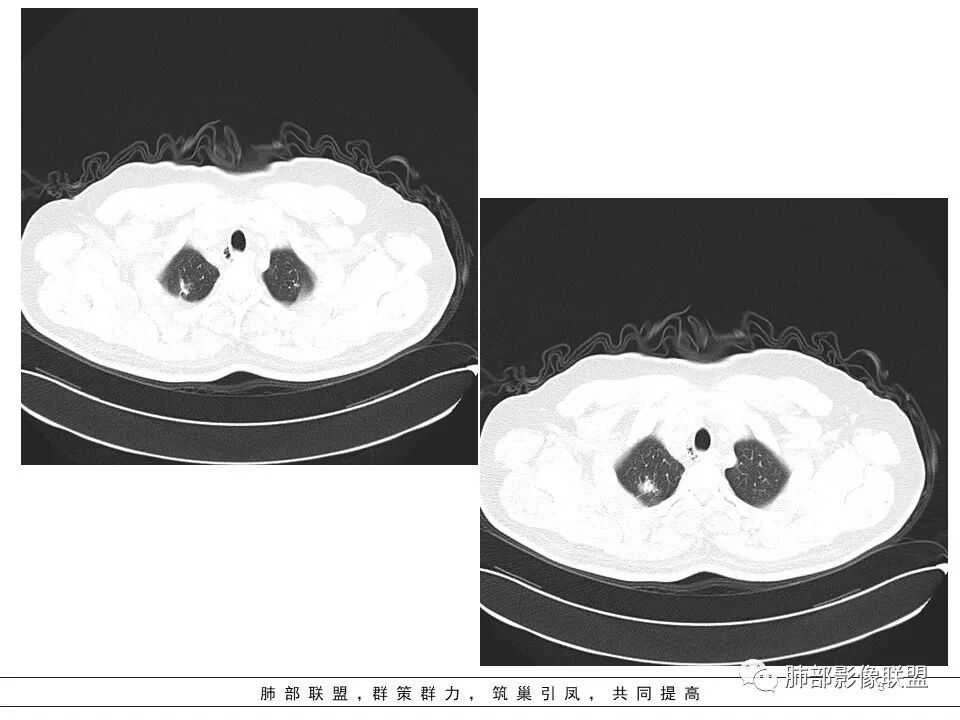

影像,气管憩室,两肺尖都有病灶,长索条

右肺上叶病灶两部分

左肺尖及右肺病灶附近见小斑点,边界尚清

遗憾的是:层厚太厚,无重建

这些是否是边界清楚GGO?

1、病灶整体形态不是类圆形,边缘凹陷、平直为主,长轴重建可能更明显,长索条,附近卫星灶,左肺尖有类似小高密度影;按常规:首先要考虑结核

南边:2、不踏实的地方:GGO是不是容积效应所致?如果薄层,边界清楚GGO,就考虑继发瘢痕癌

因此我们需要的是:薄层、重建,看GGO边缘、看整体形态

南边:瘢痕癌就需要薄层、重建观察更妥当

生来征服~浪子:部分层面彭隆的挺明显。